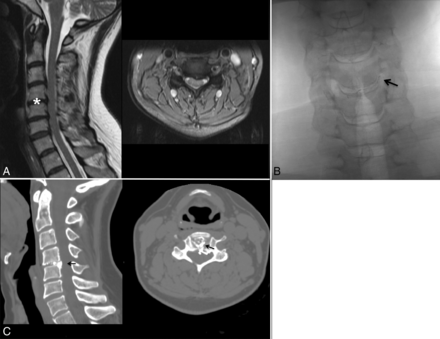

Treatment of a CDH in a 45-year-old woman with left brachialgia (VAS = 7). A, T2-weighted sagittal and T2*-weighted axial MR images show a C4–C5 left posterolateral disk herniation. Note also other asymptomatic disk bulging at the C3–C4, C5–C6, and C6–C7 levels. Anteroposterior radiograph (B) and CT axial image (C) obtained at the end of the procedure confirm the proper distribution of RGE in the treated disk, especially in the herniated portion (arrows).